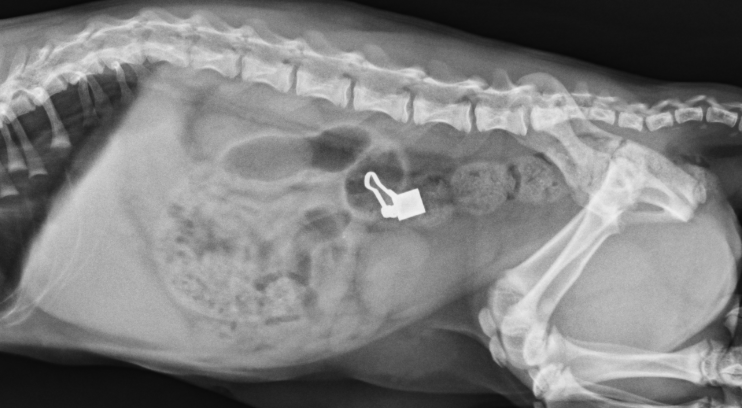

下の写真は当院で検査したX線検査での写真になります。